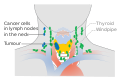

سرطان الغدة الدرقية

سرطان الغدة الدرقية، هو سرطان يتطور من أنسجة الغدة الدرقية.[1] وهو مرض تنمو فيه الخلايا بطريقة غير طبيعية مع احتمالية انتشارها إلى مناطق أخرى في الجسم.[7][8] قد تشمل الأعراض انتفاخ أو تورم في العنق.[1] قد يحدث السرطان أيضاً في الغدة الدرقية بعد انتشاره من أماكن أخرى، وفي هذه الحالة لا يُصنف كسرطان غدة درقية.[3]